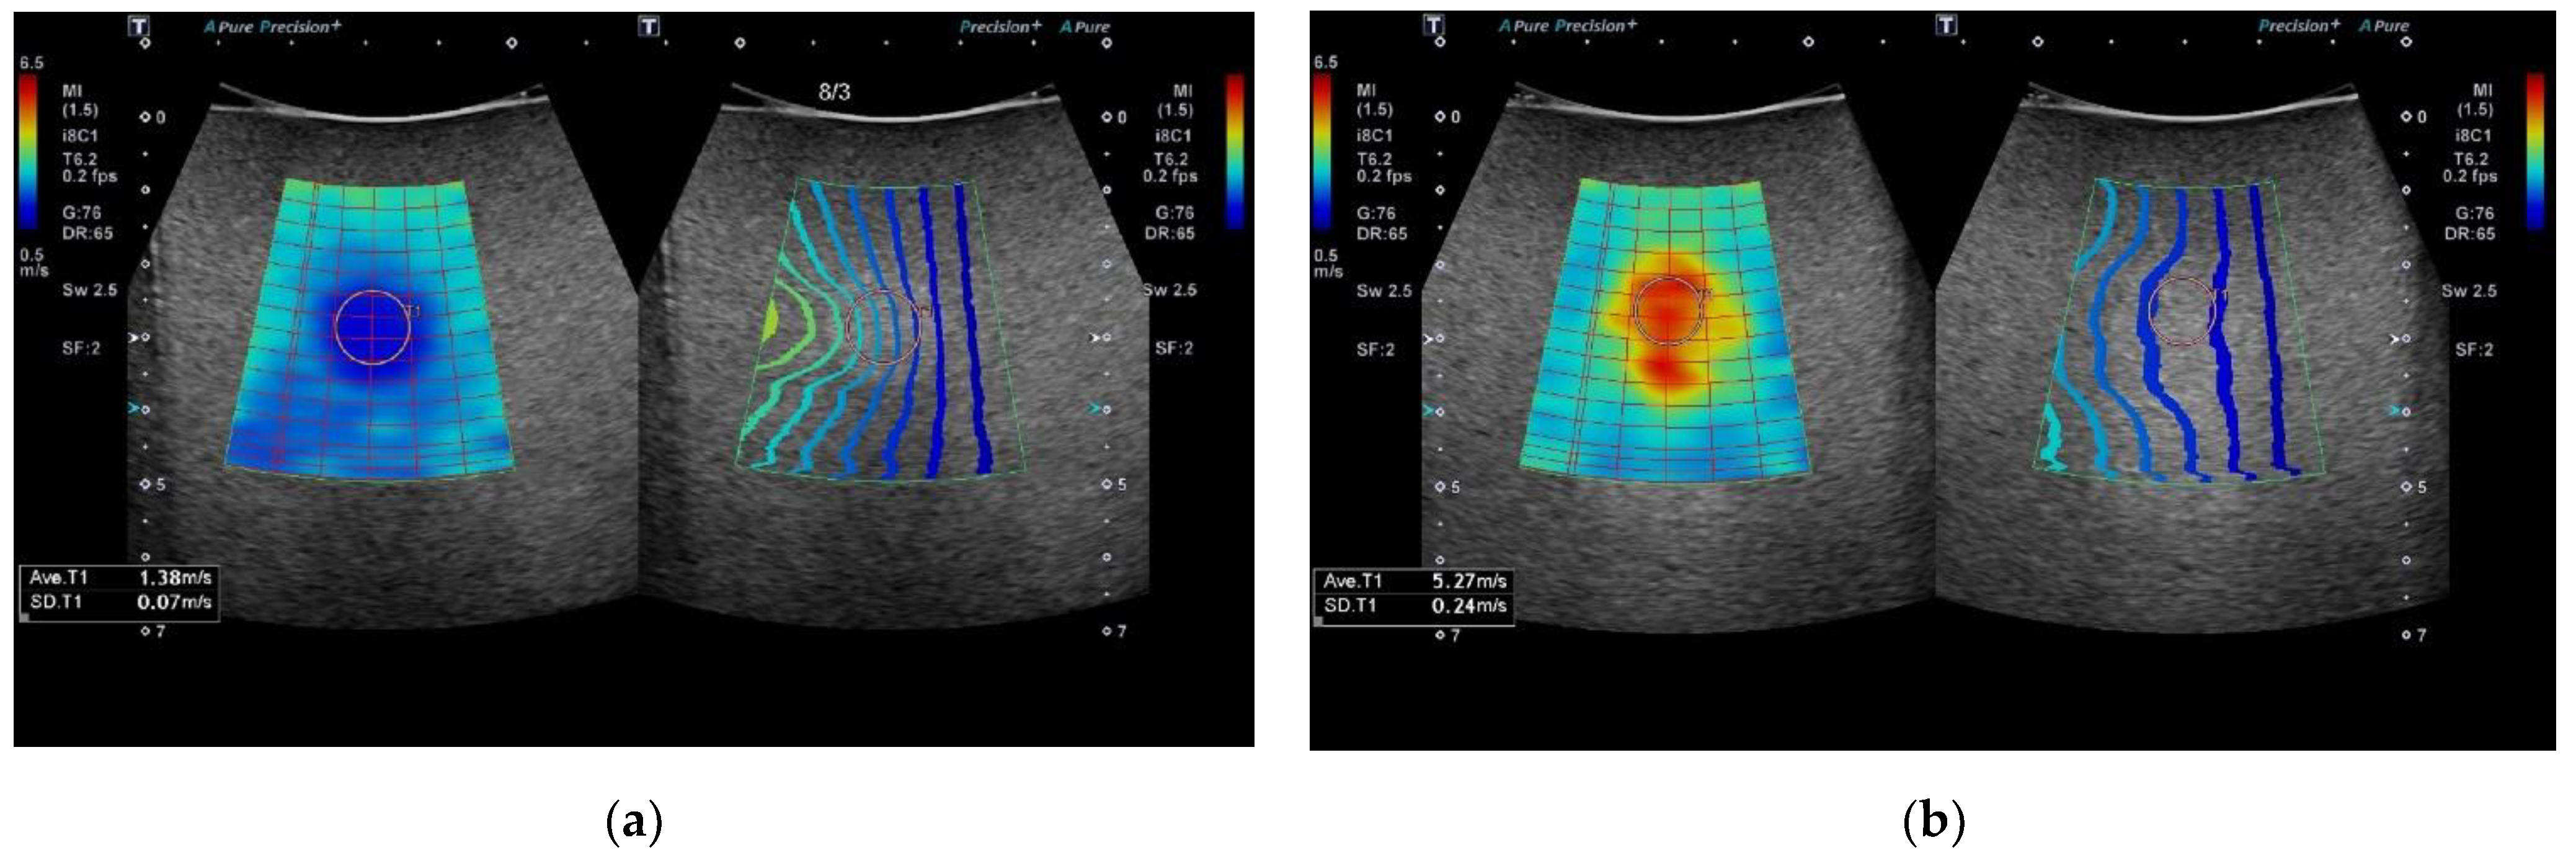

Modern 2D-SWE systems now incorporate software tools to assist operators to visually assess the stability of the acquired SWV and to inform them of the ideal placement of the sampling region of interest (ROI) box [21]. Alongside a 2D colour-coded map of tissue stiffness, a novel approach provided by some manufacturers is the addition of a “propagation contour map” (Figure 1), which uses a series of contour lines to depict shear wave arrival times at different anatomical points in the tissue being assessed [22,23]. Regions in the image displaying parallel contour lines indicate shear waves are propagating smoothly with minimum variability [21]. These two images provide complementary information designed to produce a visual indicator of the best acquisitions to select for quantitative analysis and to optimise the placement of the ROI sampling box in an area free of significant artefacts. Operators utilising 2D-SWE technology need to have confidence that any derived measurements are a true representation of the tissue being sampled and have a good understanding of the factors that can introduce variability. Thus allowing them to take steps to minimise these at the time of imaging.

Figure 1.

2D-SWE Ultrasound elastography display of two phantom targets using circular ROI (a) Type IV (85 kPa) and (b) Type I (10 kPa). Each image display is split into the parametric colour map on the left, (higher SWV coded as red/orange and slower SWV as blue/green) and reliability propagation map on the right (parallel lines indicating increased reliability).

The intervals between the contours on the visual propagation map are wider in regions where the shear waves travel faster and closer together when travelling slower (Figure 1). Areas of parallel contour lines represent areas in which shear waves propagate smoothly and indicate that the reliability of data acquisition in these areas is highest [8].